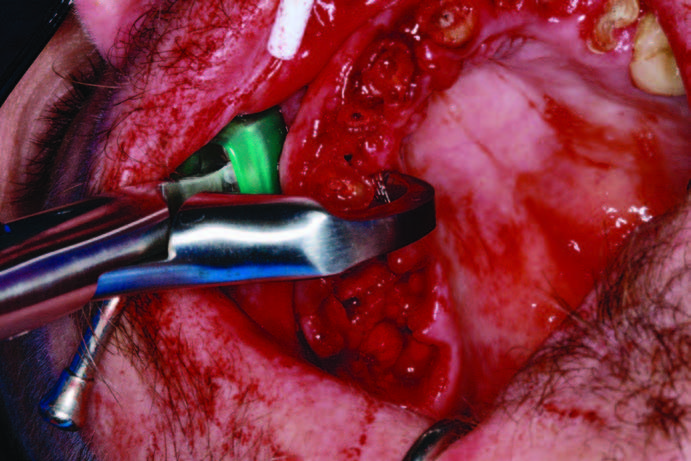

If the tooth is ankylosed or multi-rooted, then a Piezo surgical device is used to sever the periodontal ligaments (Figure 4c). It uses micro vibrations to allow the various inserts to remove bone, cut ligaments, and level osteotomies with a minimum of bleeding. It practically stops bleeding due to the movement of bone, the sealing of capillaries, and saline irrigation during the procedure. Extractions of all the mandibular teeth were done, and a caliper was used as measured in the reformatted CBCT scan (3DDX) to mark the alveolus and begin osteoplasty at each socket for the planned implant platform placement (Figure 5a). The osteoplasty was performed atraumatically using the Piezosurgery unit, and, after a cut was made buccal to lingual, a diamond insert was used to smooth all sharp edges and to level the implant sites using the Piezo surgical device (Figures 5b and 5c). A 10,600-nm CO2 laser (LightScalpel) was used to disinfect the sockets (Figure 6a). The laser uses water as its main chromophore and removes tissue by vaporization while limiting any zone of necrosis. Bacterial kill within the extraction socket, granuloma removal, and hemostasis are all accomplished with the use of this true spatially accurate laser device. In fact, use of the laser to trim tissue around abutments and permucosal healing abutments, treat peri-implantitis, and remove frena to decrease tissue pull on implants are all indicated procedures for this wavelength of CO2 laser.[3] Trimming of hypertrophic tissue during maxillary provisional placement allows for tissue modification without bleeding (Figure 6b).

The maxillary arch surgery began after the mandibular arch had healed. The full maxillary edentulation was also done using Piezosurgery and Physics Forceps. As seen in Figure 9, the lingual beak and labial bumper atraumatically “lift” the tooth out of the socket while maintaining the buccal plate. If sectioning of the tooth is required, or if purchase points need to be created for the forceps beak, then this forceps technique can allow for efficient root removal. After the extractions, the sockets were grafted with LifeNetHealth bone (Salvin Dental Specialties), and Mem-Lok type I collagen fiber membranes (BioHorizons) were used over the grafted maxilla due to the need to maintain graft coverage for 26 to 38 weeks. This material was also chosen because of its macromolecular pore size and its easy adaptation to the surgical site. After healing for 4 months, the maxillary implants were virtually planned using a new CBCT scan that first scanned the denture in with fiduciary markers (Suremark) placed and then the denture was scanned separately. This dual scan protocol (as directed by 3DDX) permits deluxe reformatting so that implants can be planned with the upper denture in a separate color, allowing for proper 3-D placement of implants within the confines of the approved occlusal construct (Figure 10). After fine-tuning services, a mucosal- born surgical guide was fabricated with maxillary implants placed for the most optimal A-P spread. The guide tubes, stabilization pins, and quality control were done by 3DDX (Figure 11). The bilateral subantral sinus augmentation was not done in order to accommodate the grandparents’ budget. The maxillary arch was grafted, and an immediate denture was delivered.